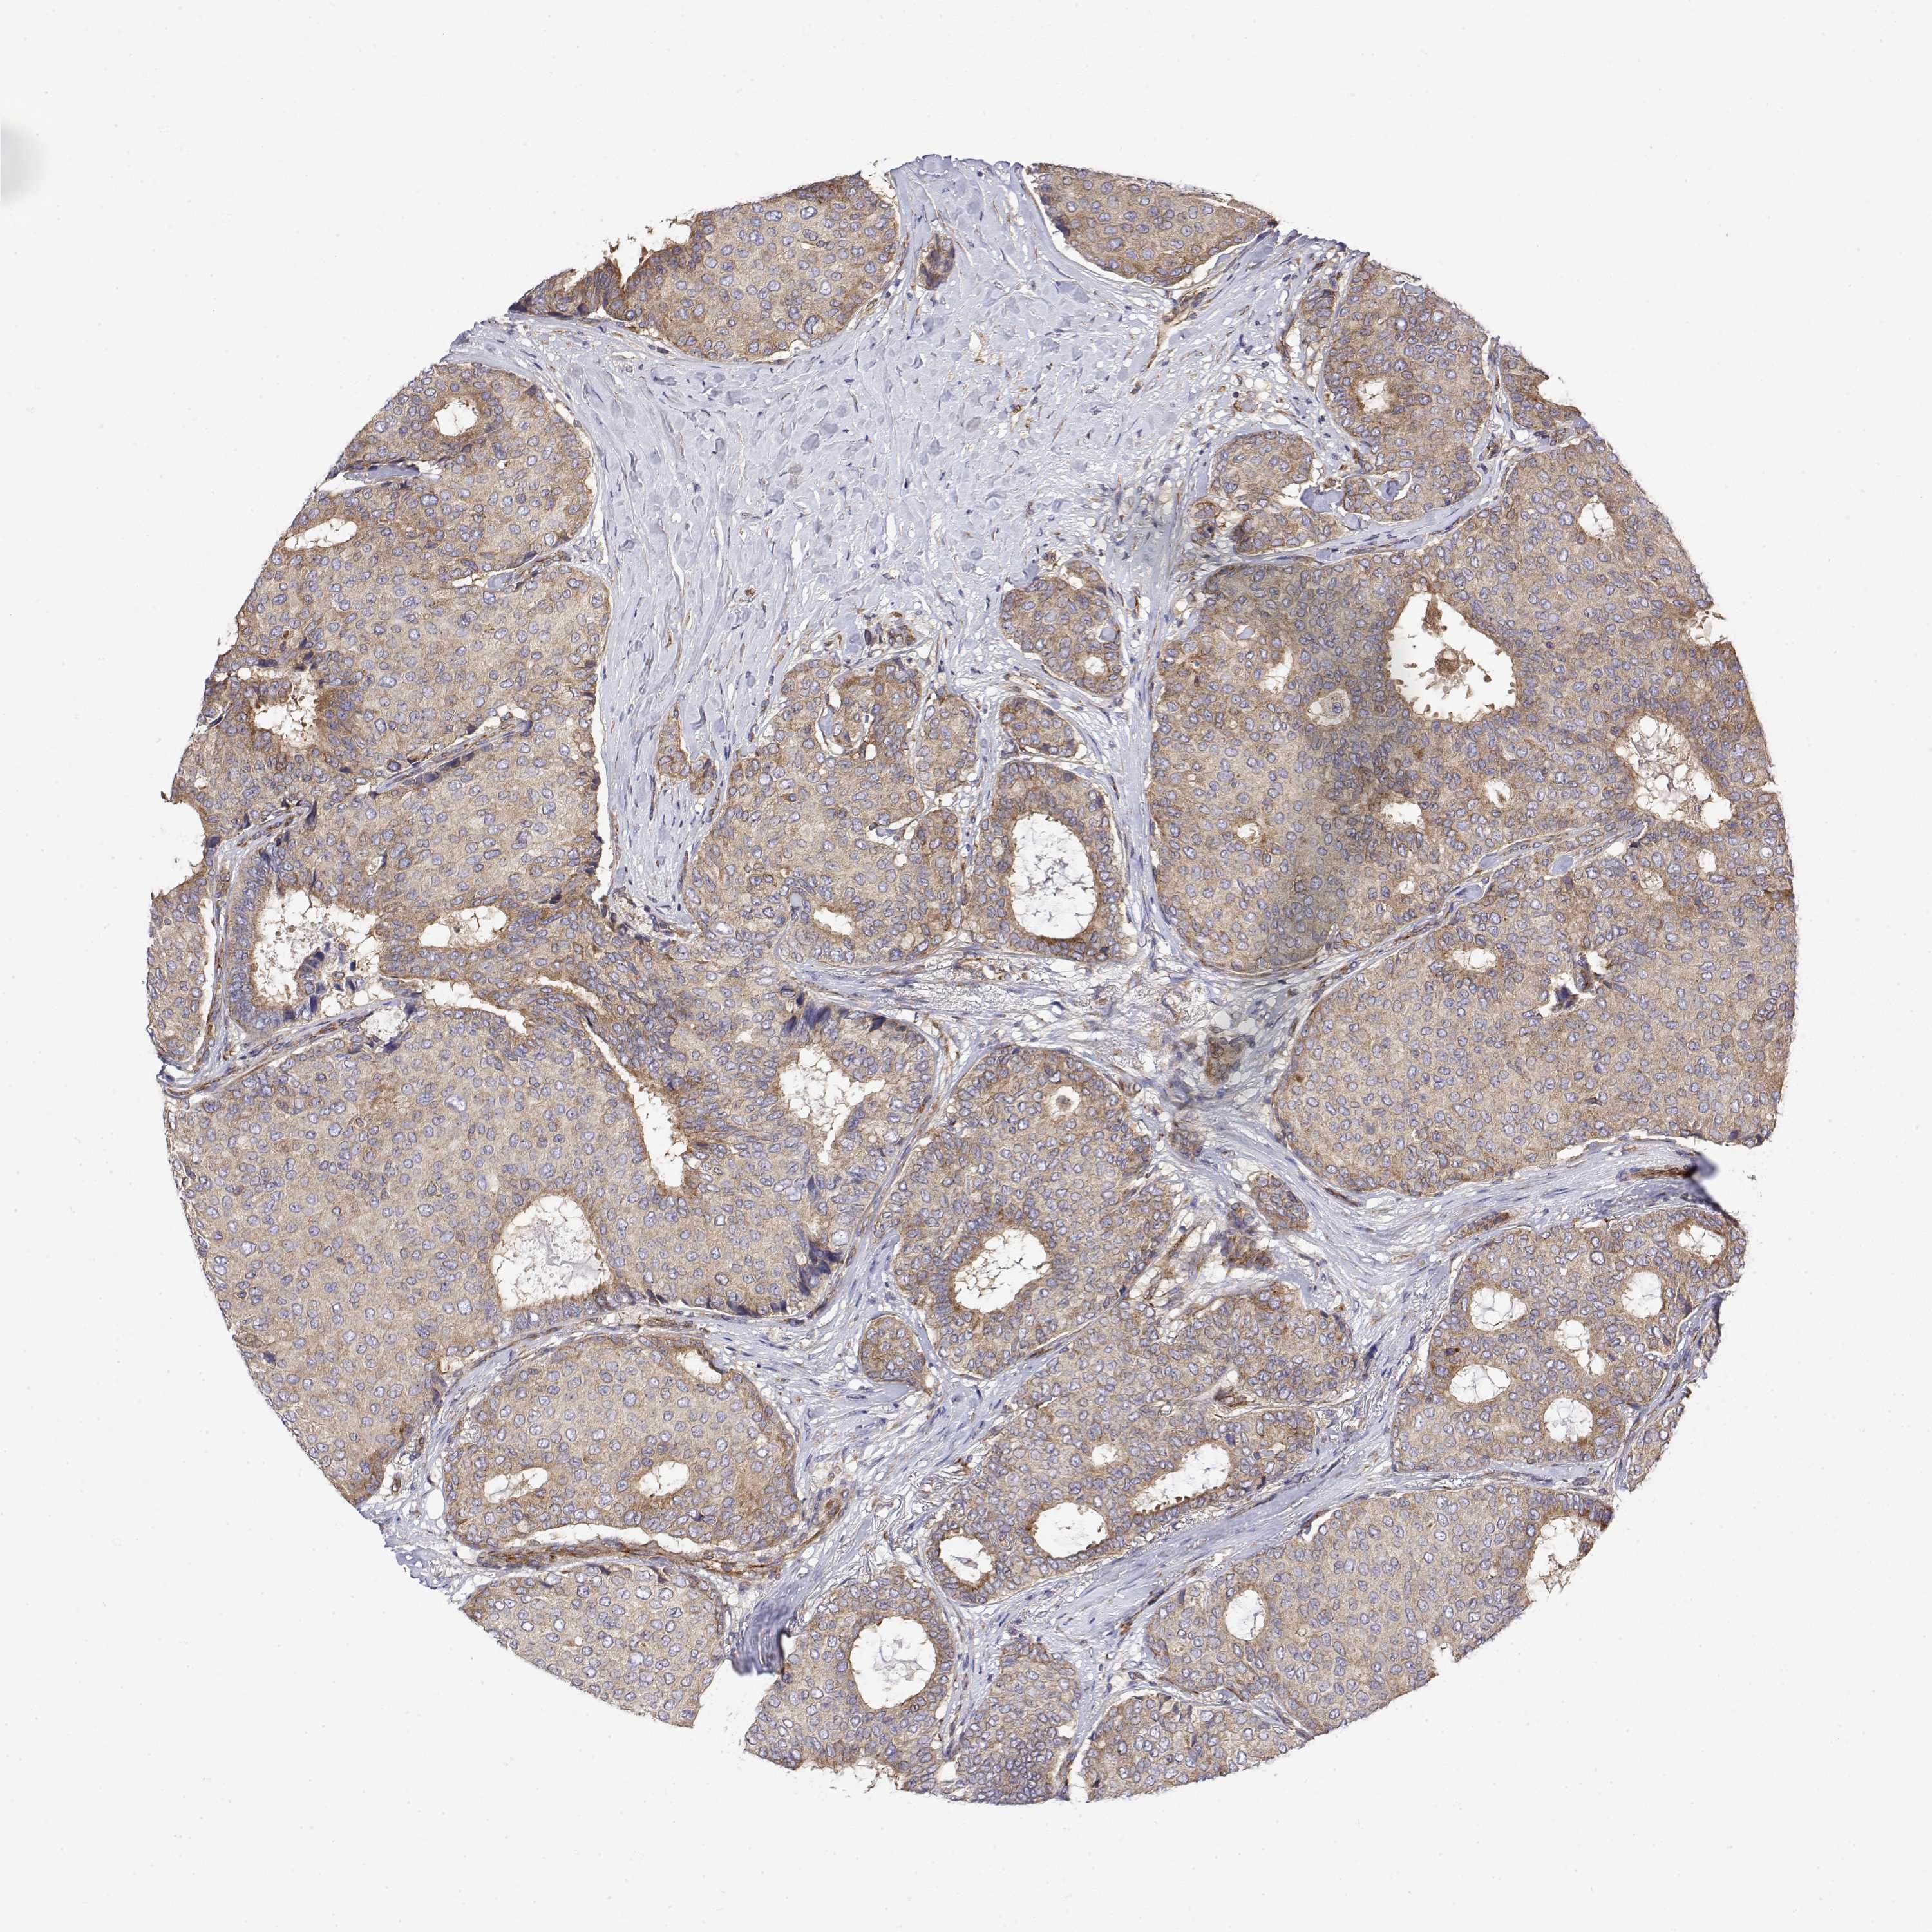

CANCER BREAST CANCER Show tissue menu

BRCA TCGA BRCA VALIDATION PROTEIN EXPRESSION